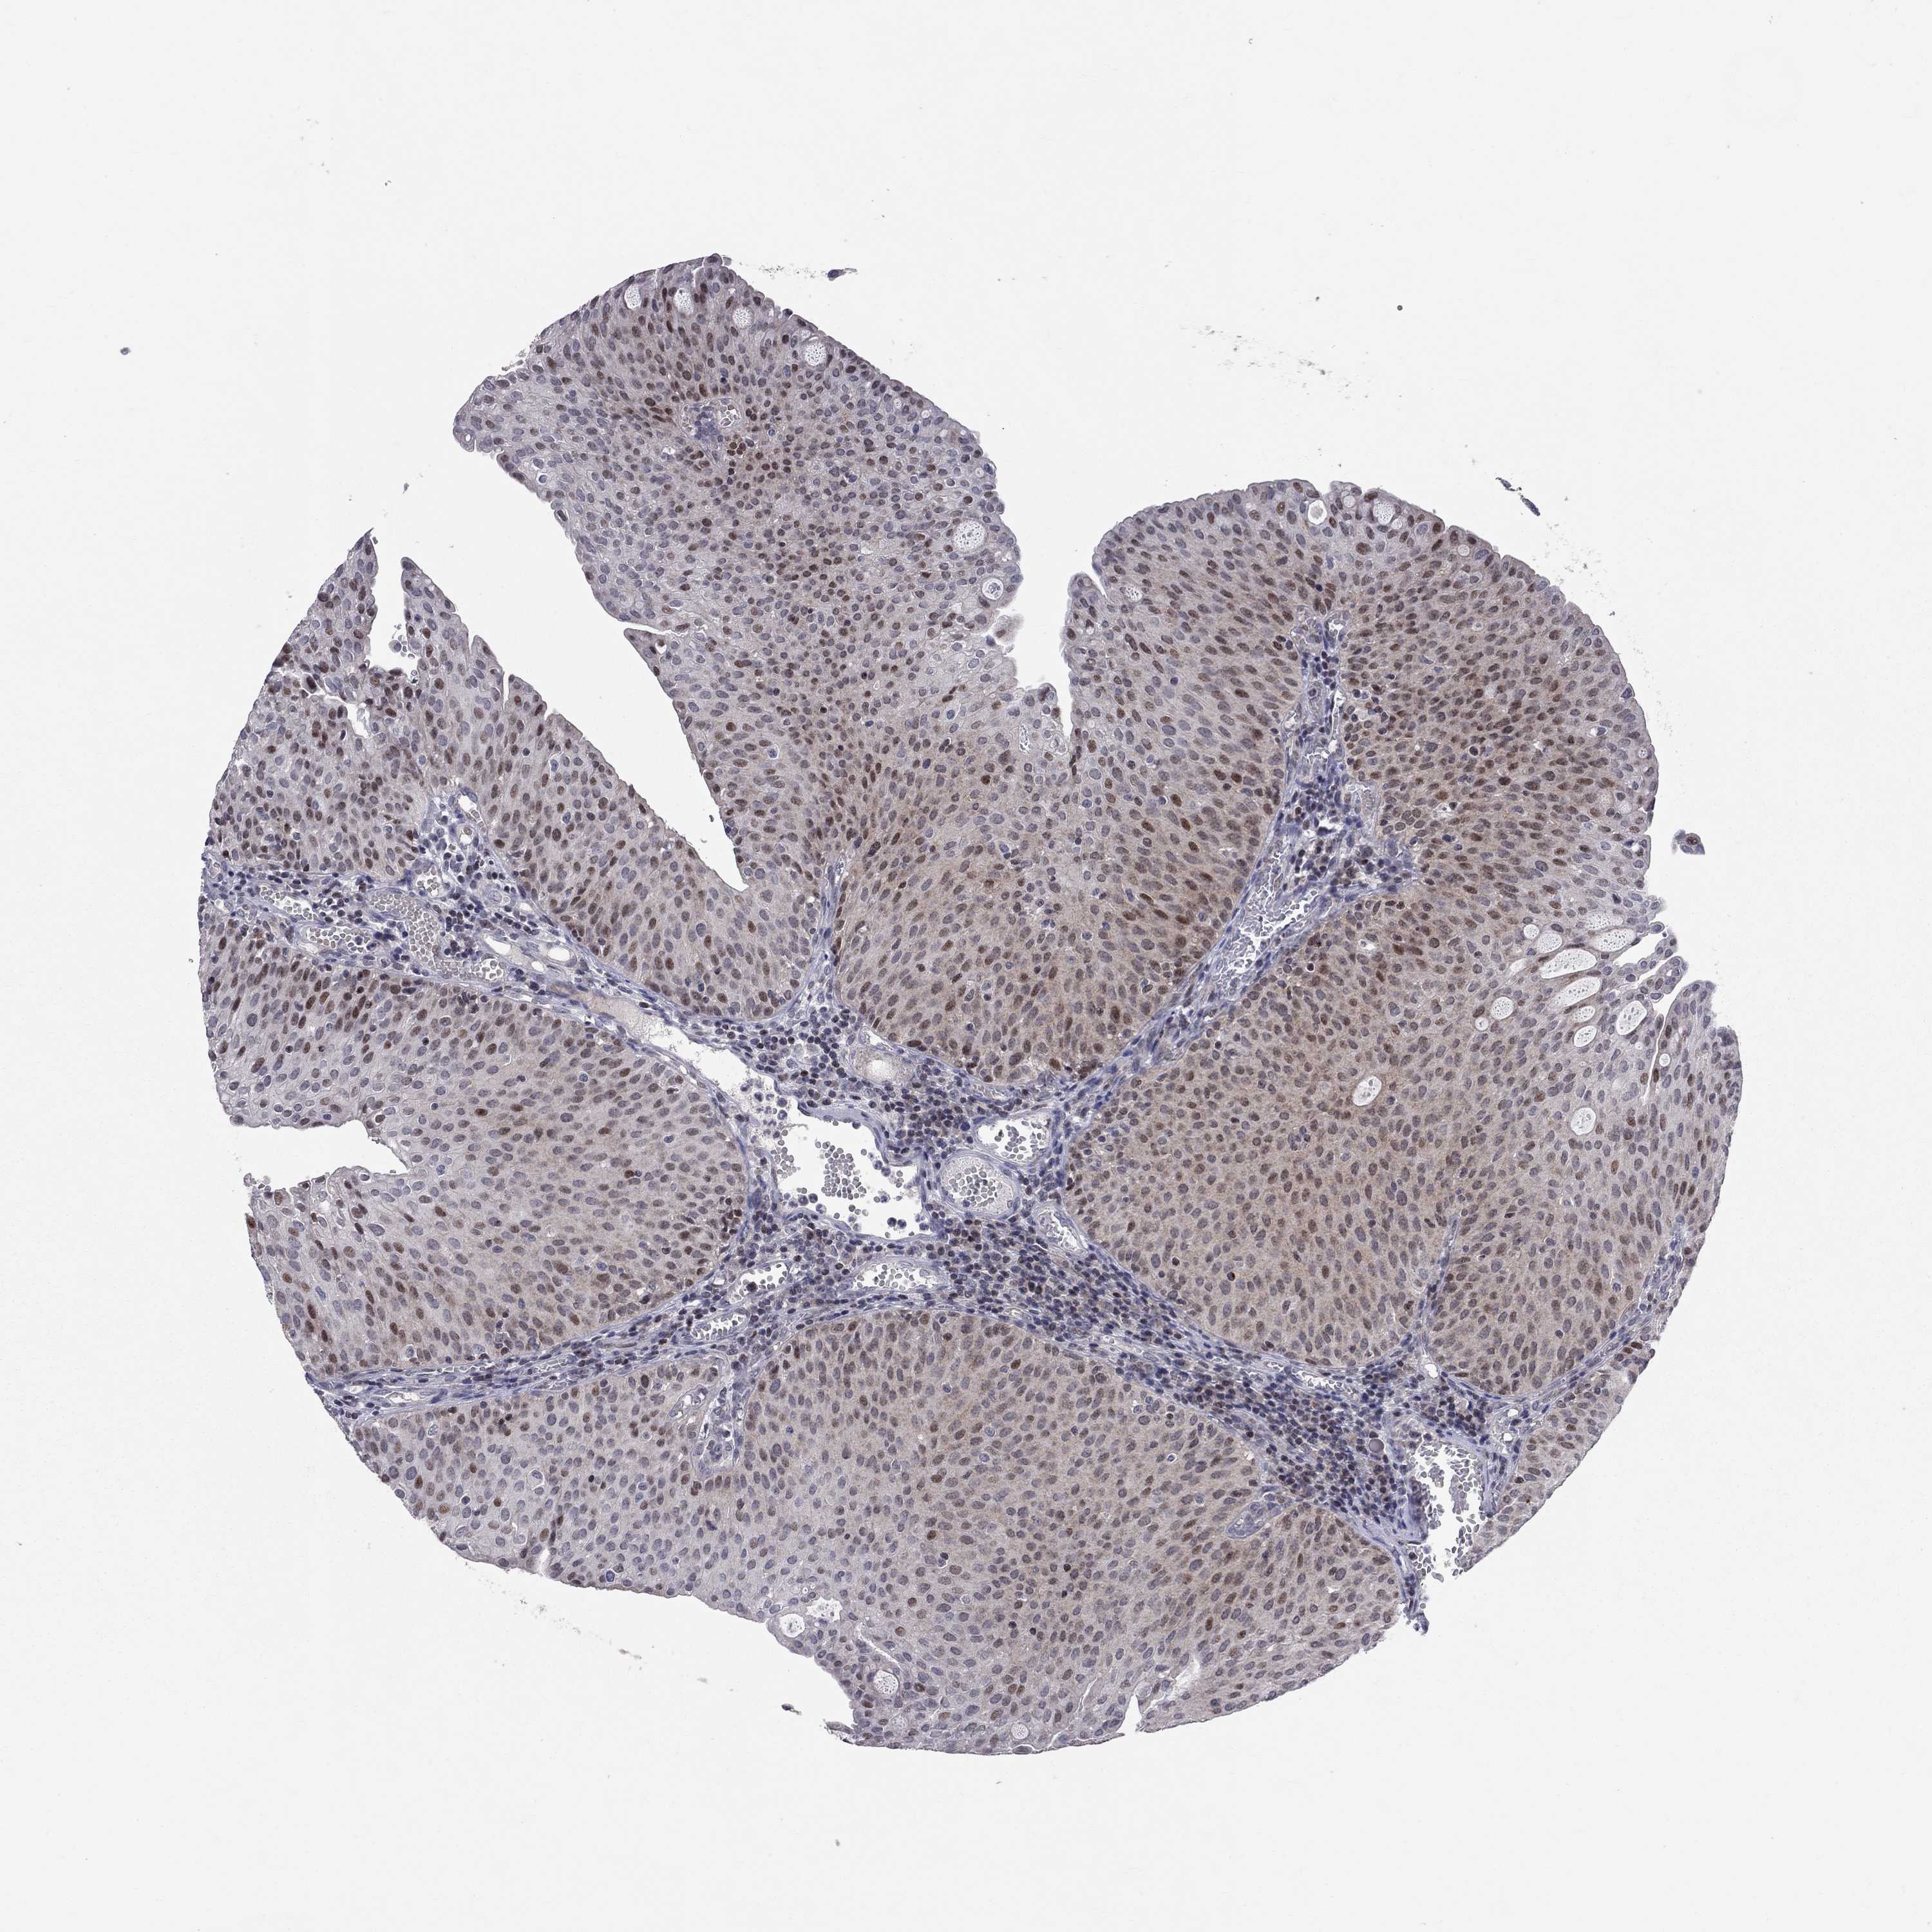

UROTHELIAL CANCER - Protein expressioni

A mouse-over function shows sample information and annotation data. Click on an image to view it in a full screen mode. Samples can be filtered based on level of antibody staining by selecting one or several of the following categories: high, medium, low and not detected. The assay and annotation is described here.

Note that samples used for immunohistochemistry by the Human Protein Atlas do not correspond to samples in the TCGA dataset.

Antibody stainingi

Antibody staining in the annotated cell types in the current human tissue is reported as not detected, low, medium, or high, based on conventional immunohistochemistry profiling in selected tissues. This score is based on the combination of the staining intensity and fraction of stained cells.

Each image is clickable and will lead to virtual microscopy that enables deeper exploration of all samples and also displays staining intensity scores, fraction scores and subcellular localization as well as patient and tissue information for each sample.

Antibody HPA052052

Antibody CAB005583

Antibody CAB072336

Staining

High

Medium

Low

Not detected

Intensity

Strong

Moderate

Weak

Negative

Quantity

>75%

75%-25%

<25%

None

Location

Nuclear

Cytoplasmic/membranous

Cytoplasmic/membranous,nuclear

Urothelial carcinoma, High grade

Urothelial carcinoma, Low grade

Urothelial carcinoma, NOS